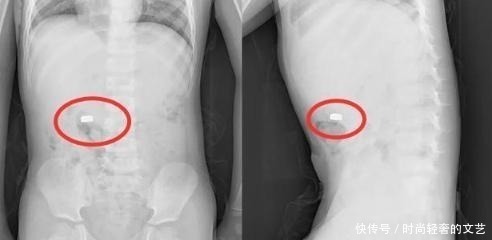

当孩子认为自己做了一件特别了不起的事情和妈妈进行“炫耀”时,他开心地告诉妈妈自己的“小秘密”,自己将会动的电池吃了,我是不是很厉害,当张女士听到之后,吓的妈妈立即带孩子去了医院,赶紧对孩子进行检查。由于孩子送去的及时,电池还没有被腐蚀。其实,在日常的生活中,很多的危险都是在我们不注意的时候发生的,如果家长不在意的话,那么可能会危害到孩子的健康,所以,一定要多注意。